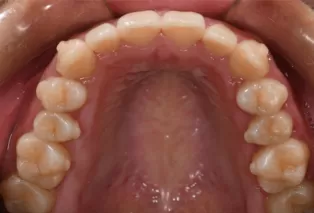

Photos intra-orales